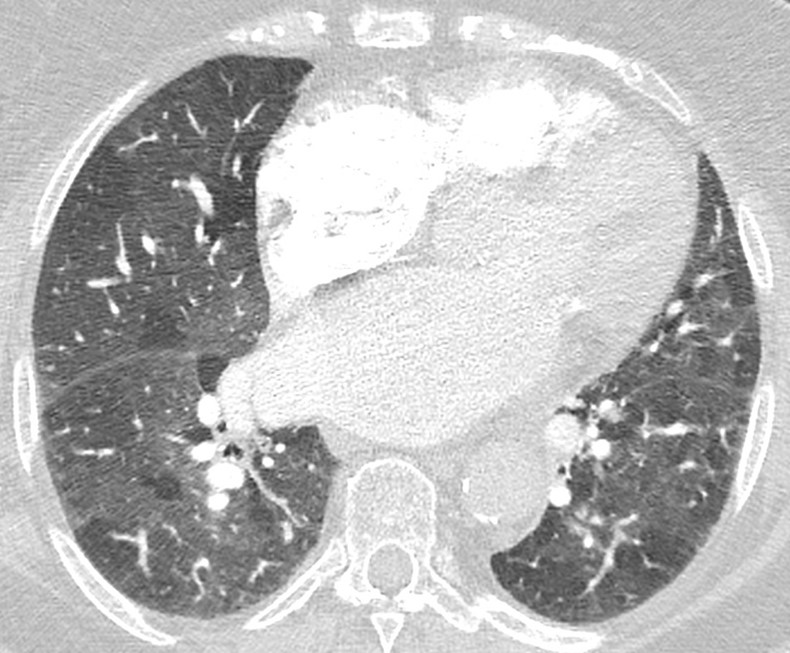

Centrilobular ground-glass nodules

Nodules with centrilobular distribution locate a few millimeters away from the pleural surface and fissures, without direct contact with them. Diffusely distributed, poorly defined centrilobular ground-glass nodules are commonly observed in patients with idiopathic PAH. These nodules correspond to cholesterol granulomas resulting from the ingestion of red blood cells by pulmonary macrophages. The differential diagnosis includes hypersensitivity pneumonitis, respiratory bronchiolitis, follicular bronchiolitis, and long-standing left-to-right shunt. It is worth noting that centrilobular ground-glass nodules, along with tortuous corkscrew vessels, can also be observed in pulmonary capillary hemangiomatosis (PCH) and pulmonary veno-occlusive disease (PVOD).